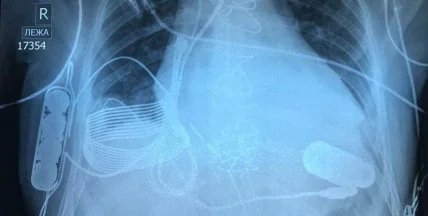

Более 50 лет назад врачи впервые имплантировали механический сердечный насос, известный как устройство желудочковой поддержки (ventricular assist device, VAD), в грудную клетку пациента, сердце которого не могло самостоятельно перекачивать кровь. С тех пор устройства спасли бесчисленное количество жизней. Теперь технология вышла на новый уровень: ученым впервые удалось вживить в грудь 24-летнего мужчины из Казахстана, страдающего от сердечной недостаточности последней стадии, устройство, которое заряжается беспроводным способом. Операция была проведена в Национальном исследовательском центре кардиохирургии в Астане, говорится в сообщении израильской технологической компании Leviticus Cardio.

Беспроводной VAD не нуждается в проводе питания благодаря системе зарядки, созданной израильской технологической компанией Leviticus Cardio. Система состоит из индуктивной катушки приемника, аккумулятора внутреннего контроллера - все они имплантированы в грудь пациента. От одного заряда устройство может проработать около восьми часов, а чтобы его зарядить, необходимо надеть жилет, содержащий внешнюю катушку, которая заряжает внутреннюю катушку с помощью электромагнетизма. Монитор на запястье помогает отслеживать уровень батареи VAD, а при разрядке или серьезных неисправностях срабатывает внутренняя вибрационная сигнализация. На случай если что-то пойдет не так с беспроводной системой зарядки, предусмотрена опция резервного питания традиционным способом.